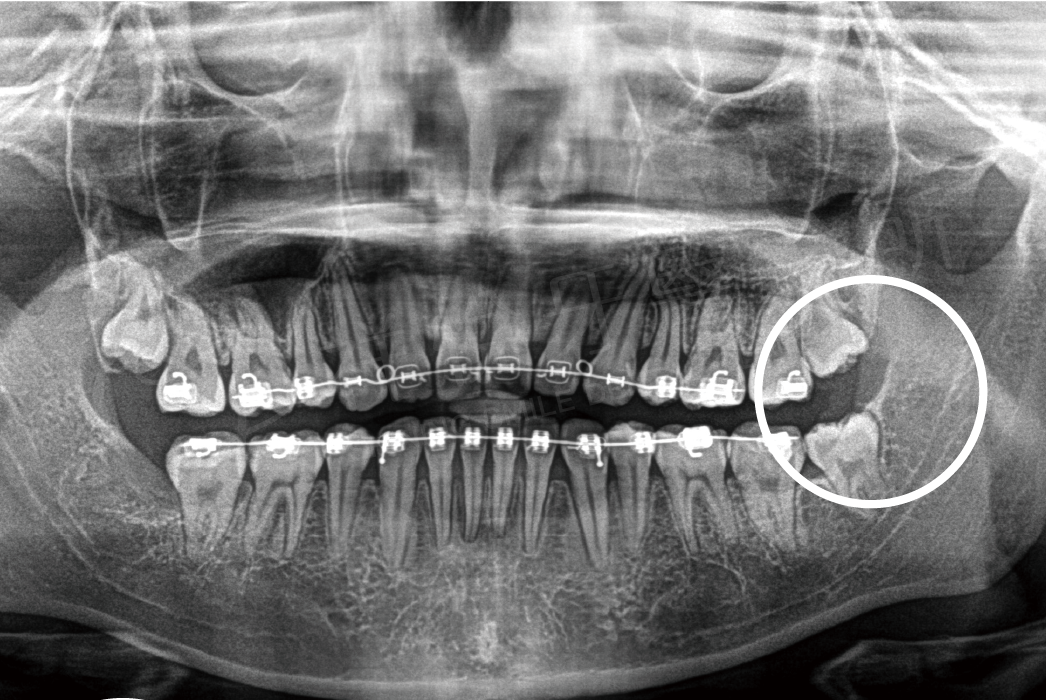

阻生齒拔除

拔牙前 拔牙後

拔牙前

拔牙後